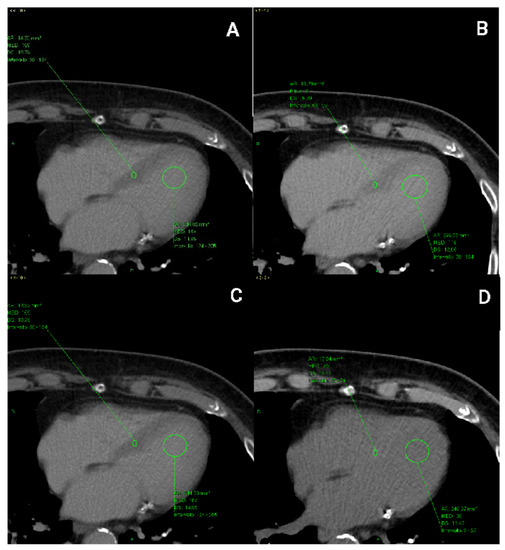

2.4. CT Image Analysis